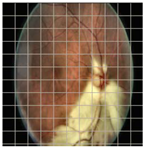

| Original Image | VGG16 | ResNet-18 | DenseNet-121 |

|---|---|---|---|

![]() | ![]() | ![]() | ![]() |

| (a) | |||

| (b) | |||

| (c) | |||

| (d) | |||